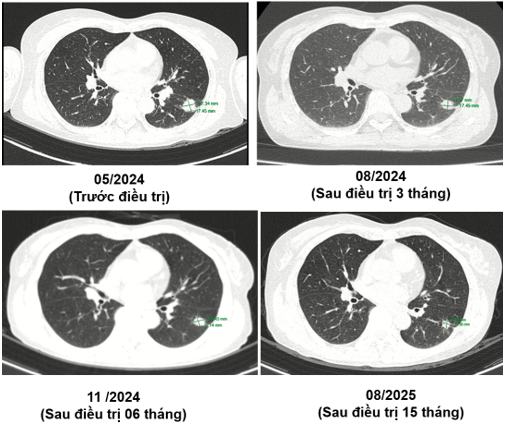

MRI sọ não sau điều trị:

Ct ngực sau điều trị:

Theo dõi định kỳ bằng lâm sàng, chụp CT ngực và MRI sọ não sau 3 tháng, 6 tháng và 15 tháng cho thấy:

- Tổn thương phổi và não giảm kích thước rõ rệt.

- Không xuất hiện tổn thương di căn mới.

- Tình trạng toàn thân ổn định, chất lượng sống được cải thiện.